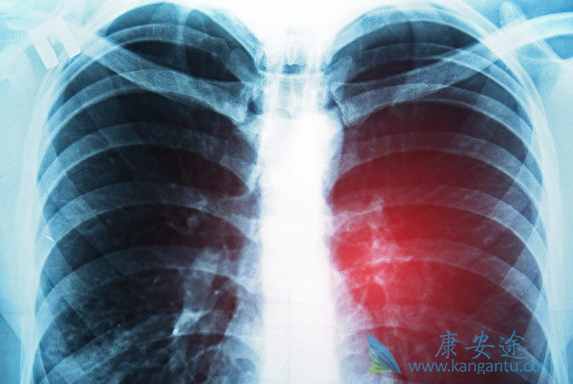

近些年来癌症疾病逐渐成为每年疾病中上升百分比例很快的疾病之一,常见的又胃癌,肠癌肺癌等,那么针对这些常见的疾病,在诊断过后,医生一般都采取哪些治疗方法帮助患者减轻病痛的折磨呢。下面小编详细的为大家介绍,肺癌最好的治疗方法是什么。

专家称对于肺癌的治疗主要是看患者的病情发展程度。我们将肺癌分早期、中期、晚期3个阶段。如果想要肺癌治愈,建议患者最好在肺癌早期的时候就开始抓紧治疗,这个阶段是肺癌能够治愈的关键节点,治疗难度并不是太大。

再次,专家称对于肺癌的治疗方法是非常重要的。一般来说,早期肺癌癌肿较小,未发生扩散转移,其最好的治疗方法为根治性手术切除。手术再结合一些中药术后调理的使用,双管齐下,康复的概率更高。如果是早期手术治疗比较好,如果是中后期放化疗治疗比较稳妥,所以说我们一定不能盲从,要根据自己的实际情况选择肺癌最好的治疗方法。